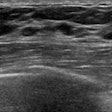

Although breast ultrasound is useful for differentiating masses, the morphologic features of benign and malignant lesions have substantial overlap. Interpretation of these images depends greatly on radiologist experience, leading to the potential for significant interobserver variability, according to the researchers.

As a result, they sought to train a convolutional neural network (CNN) to distinguish between benign and malignant breast masses on ultrasound studies. The researchers retrospectively collected 480 images of 97 benign masses and 467 images of 143 malignant masses for use in training. The deep-learning model, which was developed using the GoogLeNet CNN architecture, was then tested on a set of 120 images of patients with 48 benign masses and 72 malignant masses.